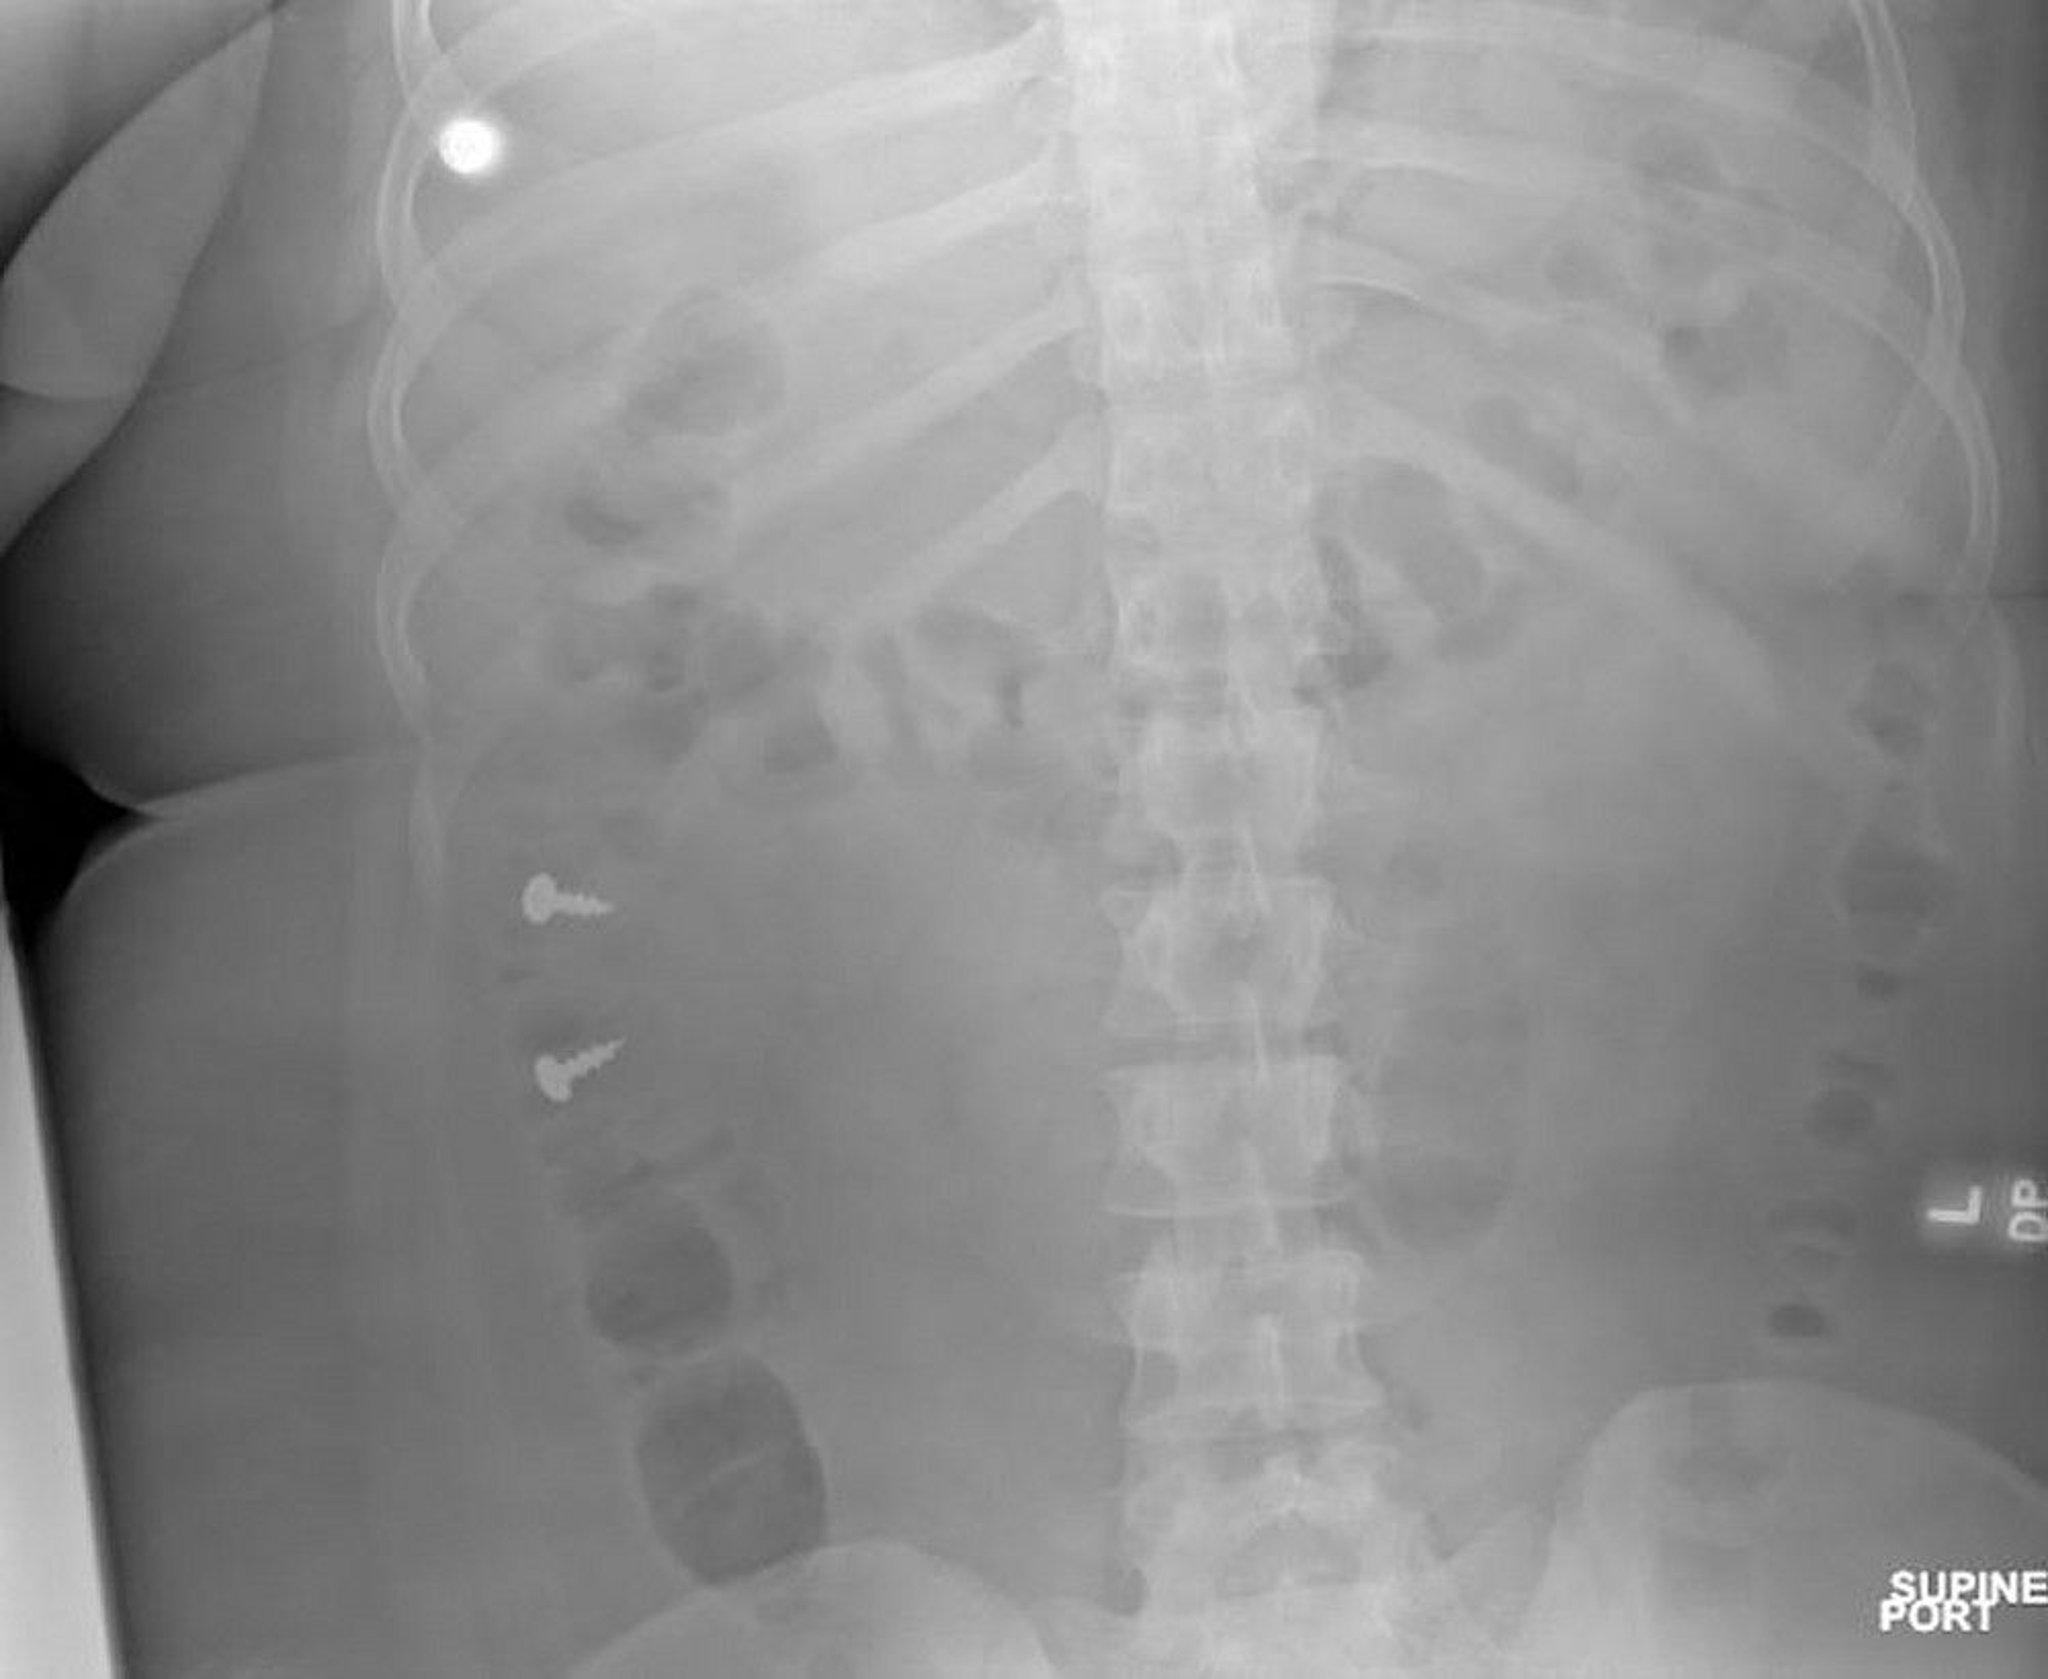

Screws in Colon (Radiograph)

Image courtesy of Zubair Malik, MD.